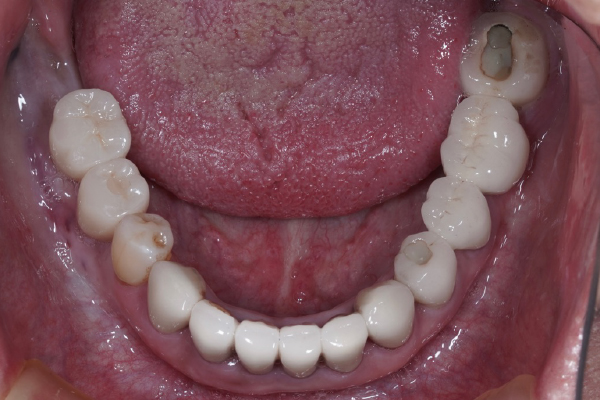

【お悩み】

奥歯を失ったまま過ごしていましたが、「手術が怖い」「本当に大丈夫なのか不安」という気持ちから治療に踏み切れずにいました。

【診断】

CT検査を行い、インプラント治療が可能な骨の状態であることを確認しました。

【治療内容】

治療前にしっかりと説明を行い、患者さまにご納得いただいたうえでインプラント治療を進めました。

【治療後】

治療後は違和感も少なく、「もっと早く相談すればよかった」とお話しされています。

【この症例のポイント】

不安を感じている方こそ、まずは状態を正確に知ることが大切です。

治療を受けるかどうかは、相談後に決めていただけます。